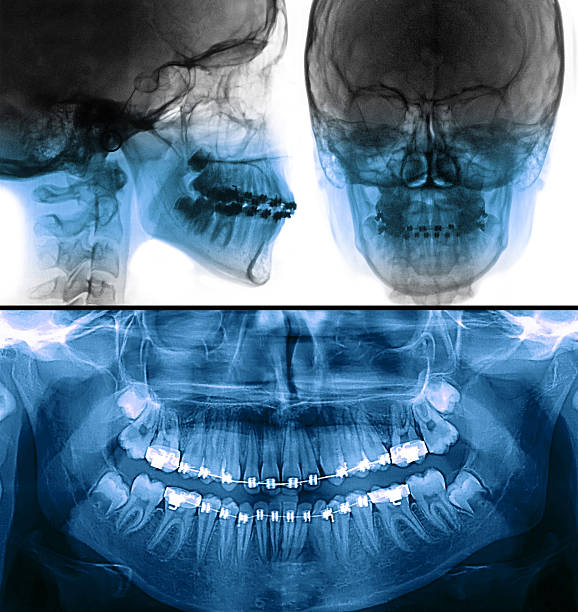

Pre-surgical imaging with CT scans assist Dr. Bagai in placing the implants in the precise location where it will allow the new tooth to merge seamlessly with your natural bite. This type of treatment plan ensures the precision and success of the implant procedure.

The 3D CT-scan is also used to assist in treatment planning, as these scans enable your dentist to better determine if dental implants are the right treatment option for you. For instance, CT imaging can help determine if the proposed implant site has sufficient bone density for a successful implant procedure.

These scanners precisely recreate, in 3D digital format, the insides of the mouth, including the structural tissues surrounding the mouth and beneath the gums. This allows the dentist to get a better picture of the entire jaw structure, assess bone quality, detect underlying pathology, determine the proper width and length of the implant to be placed, and learn the location of vital anatomical structures like the inferior alveolar nerve and the maxillary sinus.

Unlike dental x-rays that capture specifically targeted areas that the dentist will work on, the CT-scan doubles as an x-ray while accurately showcasing your entire mouth and jaw structure. Images are taken with the help of a rotating arm that captures multiple images of your head from various angles. These images are used to reconstruct 3D pictures of your internal anatomy with amazing accuracy.